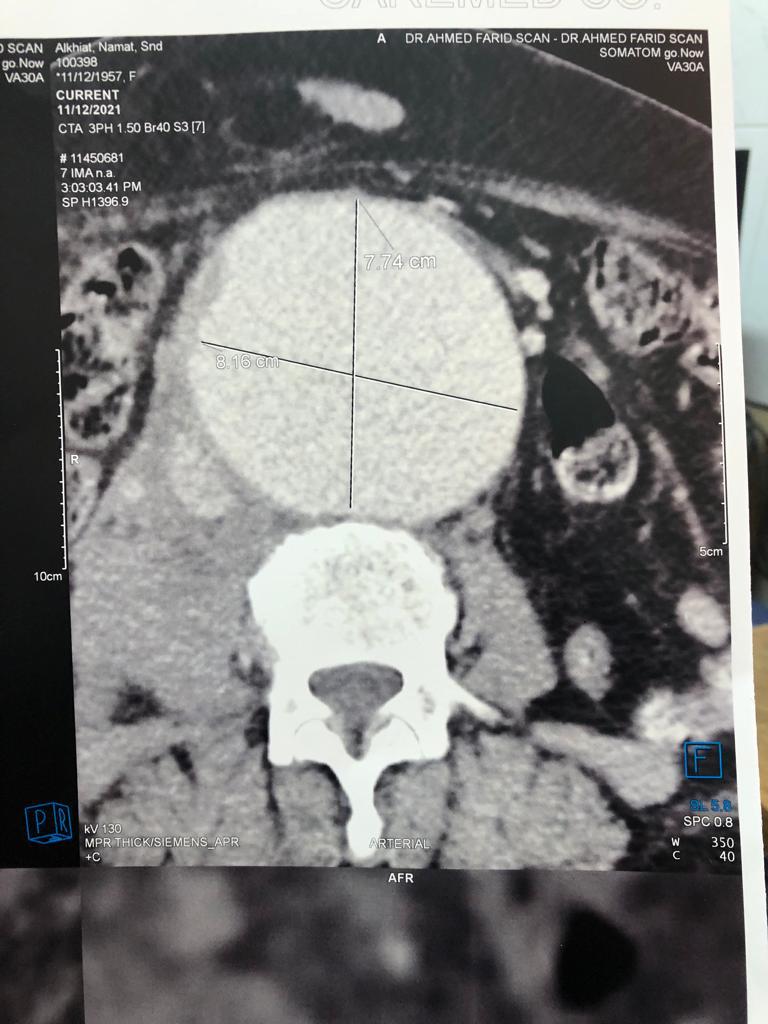

نجح الفريق الطبى بوحدة القسطره التداخلية الطرفيه بمستشفيات جامعة بنها فى تركيب دعامة مغطاة لمريضة عمرها ٦١عاما تعانى من تمدد بالشريان الاورطي البطيني ذات حجم كبير وبه تسريب دموي مما يصعب من عملية التدخل الجراحي نظرا لصعوبة الحالة وتقدم المريضة فى العمر

جديرابالذكر انه قد تم التشخيص بواسطة جهاز الأشعة المقطعيه ١٢٨ متعدد المقاطع الخاص بالشرايين التاجية بقسم الأشعة بمستشفيات جامعة بنها.